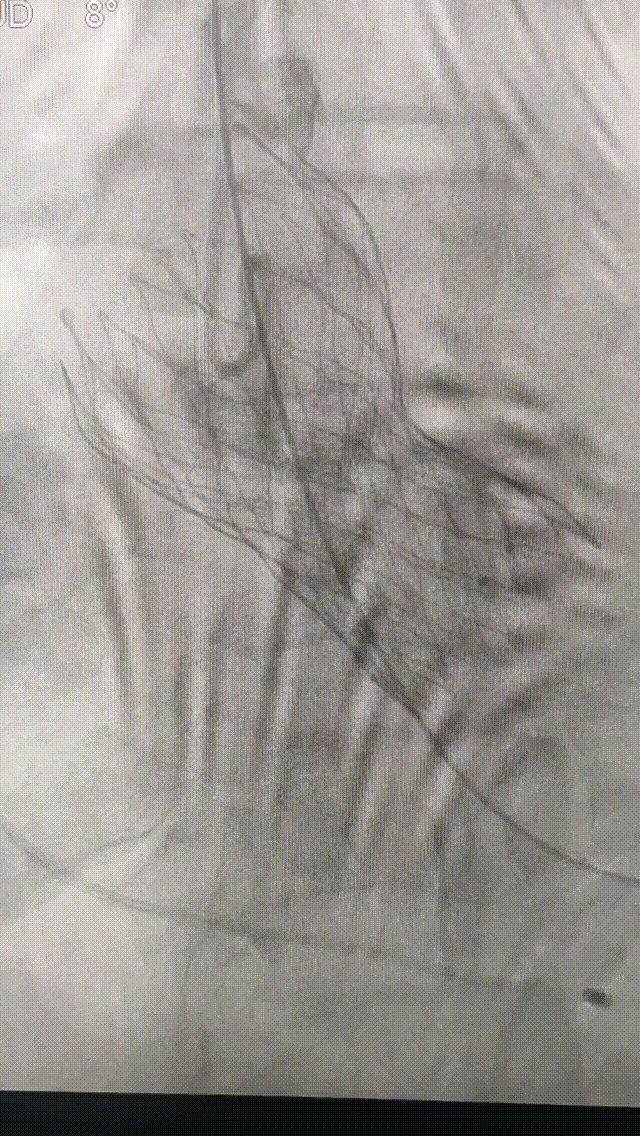

术中影像

22mm球囊预扩

造影确定瓣膜释放位置

L26号瓣膜高位释放成功